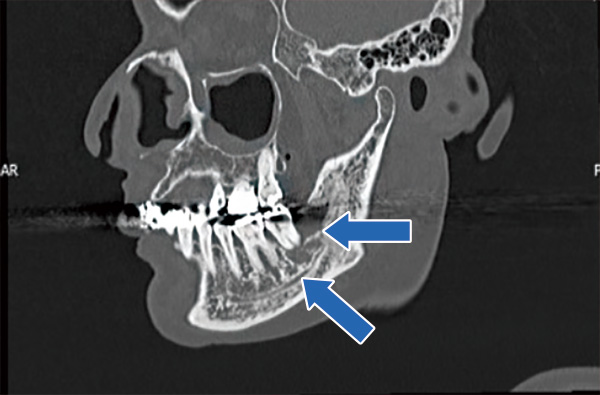

左下奥歯の内側後方に骨露出あり。

通常のエックス線写真(パノラマ)では不明瞭ですが、CTで骨吸収(矢印)が確認されます。